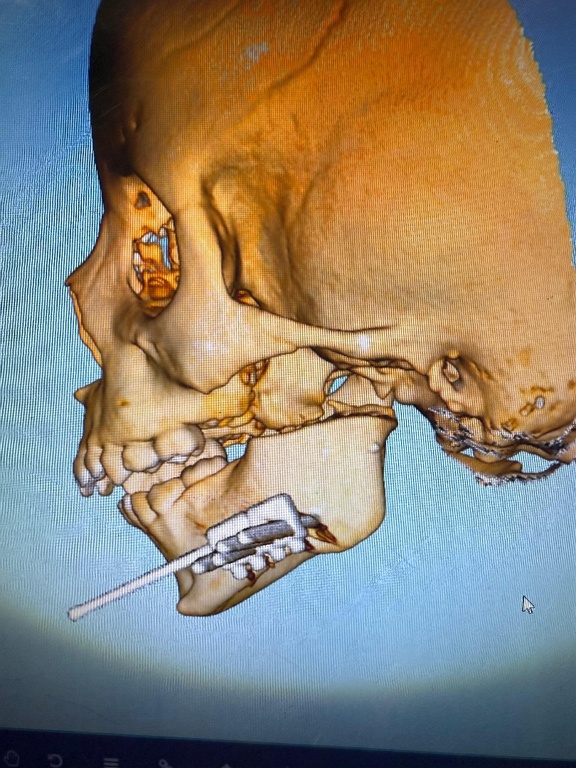

Uma criança de apenas quatro anos com deformidade grave na mandíbula passou por uma cirurgia inédita nesta terça-feira (5) no Humap-UFMS (Hospital Universitário Maria Aparecida Pedrossian), vinculado à Rede Ebserh. O procedimento marcou a estreia do uso de distratores mandibulares extraorais na instituição, um importante avanço no tratamento de deformidades faciais severas em crianças.

A paciente foi diagnosticada com anquilose temporomandibular, condição em que a articulação entre a mandíbula e a base do crânio se funde, limitando gravemente a abertura da boca. O problema teve início nos primeiros meses de vida, em decorrência de otites de repetição, e passou a comprometer o crescimento mandibular, além de prejudicar funções vitais como a alimentação e a respiração.

A cirurgia de alta complexidade mobilizou uma equipe multidisciplinar das áreas de Cirurgia Bucomaxilofacial, Cirurgia Crânio-Maxilofacial, Anestesiologia e Cirurgia Torácica. Com o distrator já instalado, a mandíbula da paciente será expandida gradualmente ao longo das próximas semanas, promovendo o desenvolvimento facial e melhorando progressivamente a deglutição e a função respiratória.

Os distratores mandibulares extraorais são dispositivos fundamentais no tratamento de deformidades provocadas por infecções, traumas ou síndromes congênitas, como Pierre Robin, Goldenhar, Treacher Collins e Crouzon. Nesses casos, a intervenção precoce é crucial para manter as vias aéreas desobstruídas e garantir o desenvolvimento adequado da face.